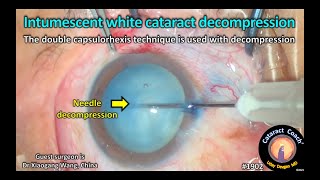

Capsulorhexis In Intumescent Cataract, Surgeon - Dr Pradip Mohanta CataractCoach™ 1902: intumescent white cataract decompression

CataractCoach™ 1902: intumescent white cataract decompression two-handed capsulorhexis technique for intumescent white cataracts

Capsulorhexis In Intumescent Cataract, Surgeon - Dr Pradip Mohanta CataractCoach™ 1902: intumescent white cataract decompression

CataractCoach™ 1902: intumescent white cataract decompression two-handed capsulorhexis technique for intumescent white cataracts